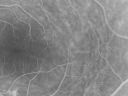

Sturge-Weber Encephalotigeminal Angiomatosis - Facial Hemangioma and Asymptomatic Ipsilateral Diffuse Choroidal Hemangioma752 views61-year-old man with Sturge-Weber syndrome with a hemangioma on the left side of his face.

VISUAL ACUITY: Vision OD is 20/50, PH 20/30; OS 20/80, PH 20/30. IOP: OD 16, OS 19.